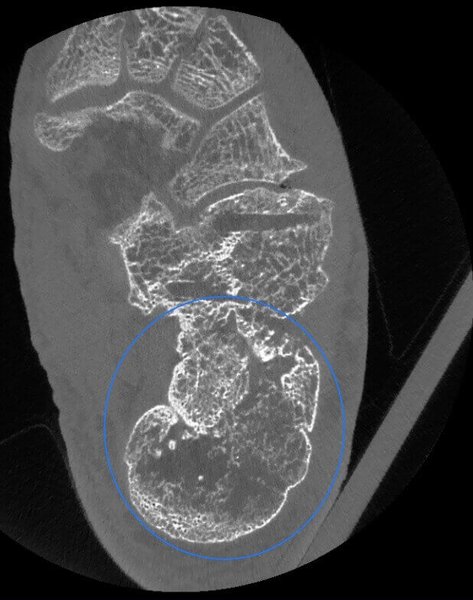

Lesione Osteocondrale in paziente con mezzo di Osteosintesi